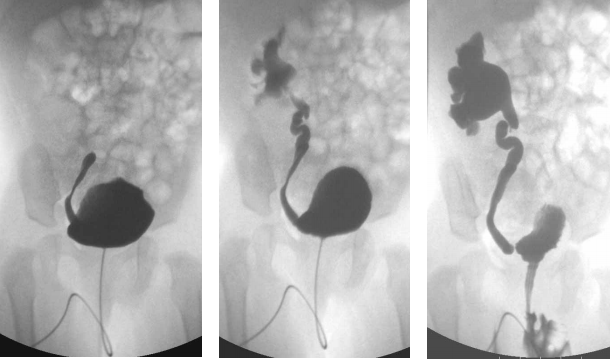

79 一位 2 歲的林小妹妹,1 年來常常發燒,尿液檢查顯示感染性尿液。醫師為她做膀胱及排尿攝影檢查, 影像如圖示。林小妹妹最可能患了什麼病?

(A)結核病(tuberculosis) (B)逆流性腎病(reflux nephropathy) (C)腎乳頭壞死(papillary necrosis) (D)急性腎盂腎炎(acute pyelonephritis)